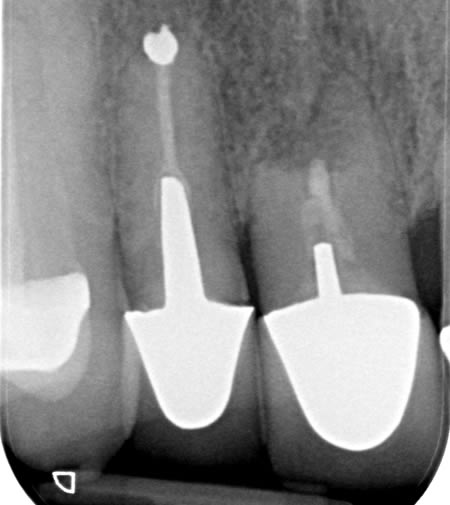

Case F

Preparation Treatment

Case G

A failed apicectomy in the UL1 was diagnosed after a history of labial draining discharge and mobility. The patient was referred to us for treatment and a diagnostic wax up was used to discuss the proposed finished crown, estimated gingival margin position and crown height with the patient.

A tooth bourn position guide allowed for predictable implant placement within the aesthetic zone. Collaboration with with Smile Dental Laboratory and clinical pictures helped to produce a great shade match and natural looking result.